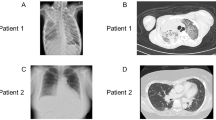

Our previously published index patient with novel hemizygous IL2RG c.172C > T;p.(Pro58Ser) missense variant [17] is currently 13-year-old male (Fig. 1a). At age 2, he started to suffer from recurrent respiratory tract infections and persistent bilateral purulent middle ear infections. He developed bronchiectasis by the age of 7. Despite normal total immunoglobulin levels, intravenous immunoglobulin (IVIG) treatment was started due to specific antibody deficiency and recurrent respiratory tract infections. Thereafter, frequency of infections has markedly reduced and no progression of bronchiectasis has been observed. Before immunoglobulin substitution, our patient’s PCR test for CMV was negative. After the start of IVIG, our patient has repeatedly tested positive for CMV-specific IgG, likely due to IVIG, but has remained negative for IgM CMV antibodies. Currently, he suffers from molluscum contagiosum with occasional secondary bacterial skin infections. His detailed clinical phenotype and genetic analysis have been described earlier [17] and were updated in the Online Resource (text and Table S3). Since the age of 7, he has showed increased amounts of γδ T cells in his peripheral blood (20–40% of CD3 + T cells), unlike his family members (Fig. 1b, c, Fig. S1a, Online Resource), while the total amount of CD3 + T cells has remained within normal range (Fig. 1b, Table S3 Online Resource). The presence of c.172C > T p.(Pro58Ser) missense variant in γδ T cells was verified by Sanger sequencing, ruling out genetic reversion (Fig. S1b, Online Resource). Expression of IL2RG p.(Pro58Ser) variant was reduced on the surface of CD4 + and CD8 + T cells and NK cells, as well as on monocytes [17]. We studied the surface expression of IL2RG (CD132) on the patient’s γδ T cells and found it to be normal when compared to healthy donors’ cells while being clearly reduced on his ⍺β T cells (CD3 + TCRγδ- cells) (Fig. 1d, e). However, the total cell-associated IL2RG was significantly reduced also in his γδ T cells (34% less than in controls), but reduction of total IL2RG expression was even more pronounced in his TCRγδ-negative T cells (51% less than in controls, Fig. S2a-b, Online Resource). Taken together, IL2RG p.(Pro58Ser) variant leads to reduced IL2RG cell surface expression on conventional CD3 + T cells, while γδ T cells express normal surface level of IL2RG.

Patient’s γδ T cells show normal surface expression of IL2RG. a Family pedigree. Index patient marked with an arrow, WT for wild type. b Patient’s total CD3 + T cell levels and percentual proportions of TCRαβ + and TCRγδ + cells of peripheral blood CD3 + T cells over time. Yellow area indicates normal range of the γδ T cells (1.9–11.7%; in-house reference range by HUSLAB), yellow line indicates the lower limit of normal CD3 + T cell absolute number (0.75 × 10^9/l; in-house reference range by HUSLAB). c TCRαβ + and TCRγδ + proportions of the patient and his family members (mean with SEM). Cell surface expression of IL2RG (CD132) in CD3 + TCRγδ + (d) and CD3 + TCRγδ- (e) cells. Patient in red, healthy donor 1 in light blue, healthy donor 2 in blue, fluorescent minus one sample in gray. Shown are representative histograms (left) and cumulative bar graphs from three independent experiments (for healthy controls n = 2 in each repeat). Graphs show mean with SEM. *p < 0.05, determined by unpaired t-test with Welch’s correction; ns, non-significant in (c–e). The figure was constructed using the following software: Microsoft Office Powerpoint (64B), GraphPad Prism (v.9.2.0), NovoExpress software, Acea